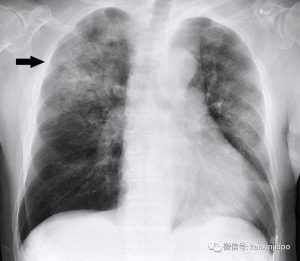

紧急通报!新加坡再发现一起疑似武汉肺炎病例

默认标题_自定义px_2021-02-23-0.png今天(1月10日),新加坡卫生部紧急发文,说新加坡又出现一起疑似武汉肺炎的病例!这名26岁的中国籍男子被检查出患有肺炎,而他不久前曾经去过武汉,但并未到访很多人怀疑中的武汉肺炎源头——华南海鲜批发市场。新加坡有关部门现在正调查男子的肺炎是否与武汉肺炎有关,但是作为预防措施,这名男子目前已被隔离、接受进一步的检测及治疗。他目前情况稳定。最近新加坡可是“谈肺炎色变”,1月3日晚上开始,所有从武汉飞往新加坡的旅客,都必须在抵达樟宜机场时接受体温检测。若发现有任何类似于肺炎的可疑病例,将被直接送往医院进行隔离,再做进一步检查。而在短短一天后的1月4日,新加坡卫生部接到第一起与武汉肺炎疫情有关的可疑病例!当时,一名近期去过武汉的3岁女童被诊断出肺炎。万幸的是,经过一系列流行病学调查、临床评估及实验室结果显示,卫生部于今天证实这名女童对非典(SARS)、中东呼吸综合征(MERS-CoV)亦呈阴性反应。因此确认她得的只是在儿童呼吸道感染中常见的呼吸管道合胞病毒(respiratory syncytial virus)。武汉肺炎“来势汹汹”,截至今年1月5日,武汉市共报告肺炎诊断患者59例,其中重症患者7例。但庆幸的是,到1月8日已经有8名患者出院。这两天,这种不明原因病毒性肺炎的“真凶”已经找到。中国的专家组认为,本次不明原因病毒性肺炎病例的病原体初步判定为新型冠状病毒。而冠状病毒有两个特点:变异的概率高及感染的动物种类广。不过,“新型”并不代表危害大。从中国目前的疾病控制和治疗情况来看,目前暂无死亡病例,患者病情稳定可控。研究人员也未发现明显的人传人现象,也没有发现医务人员感染。因此,世界卫生组织(WHO)今天也就武汉肺炎发声明,不建议限制旅行或贸易 。为避免病毒传播,大家可以采取以下措施保护自己: